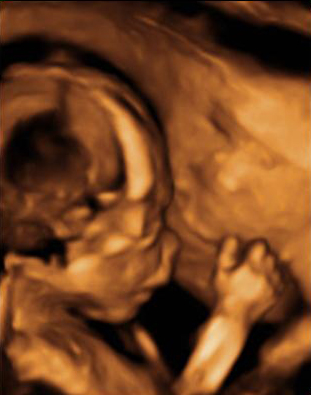

En la imagen ecográfica podemos ver el corte de la cabeza fetal donde se muestra la medición de un ventrículo cerebral aumentado de tamaño (o ventriculomegalia).